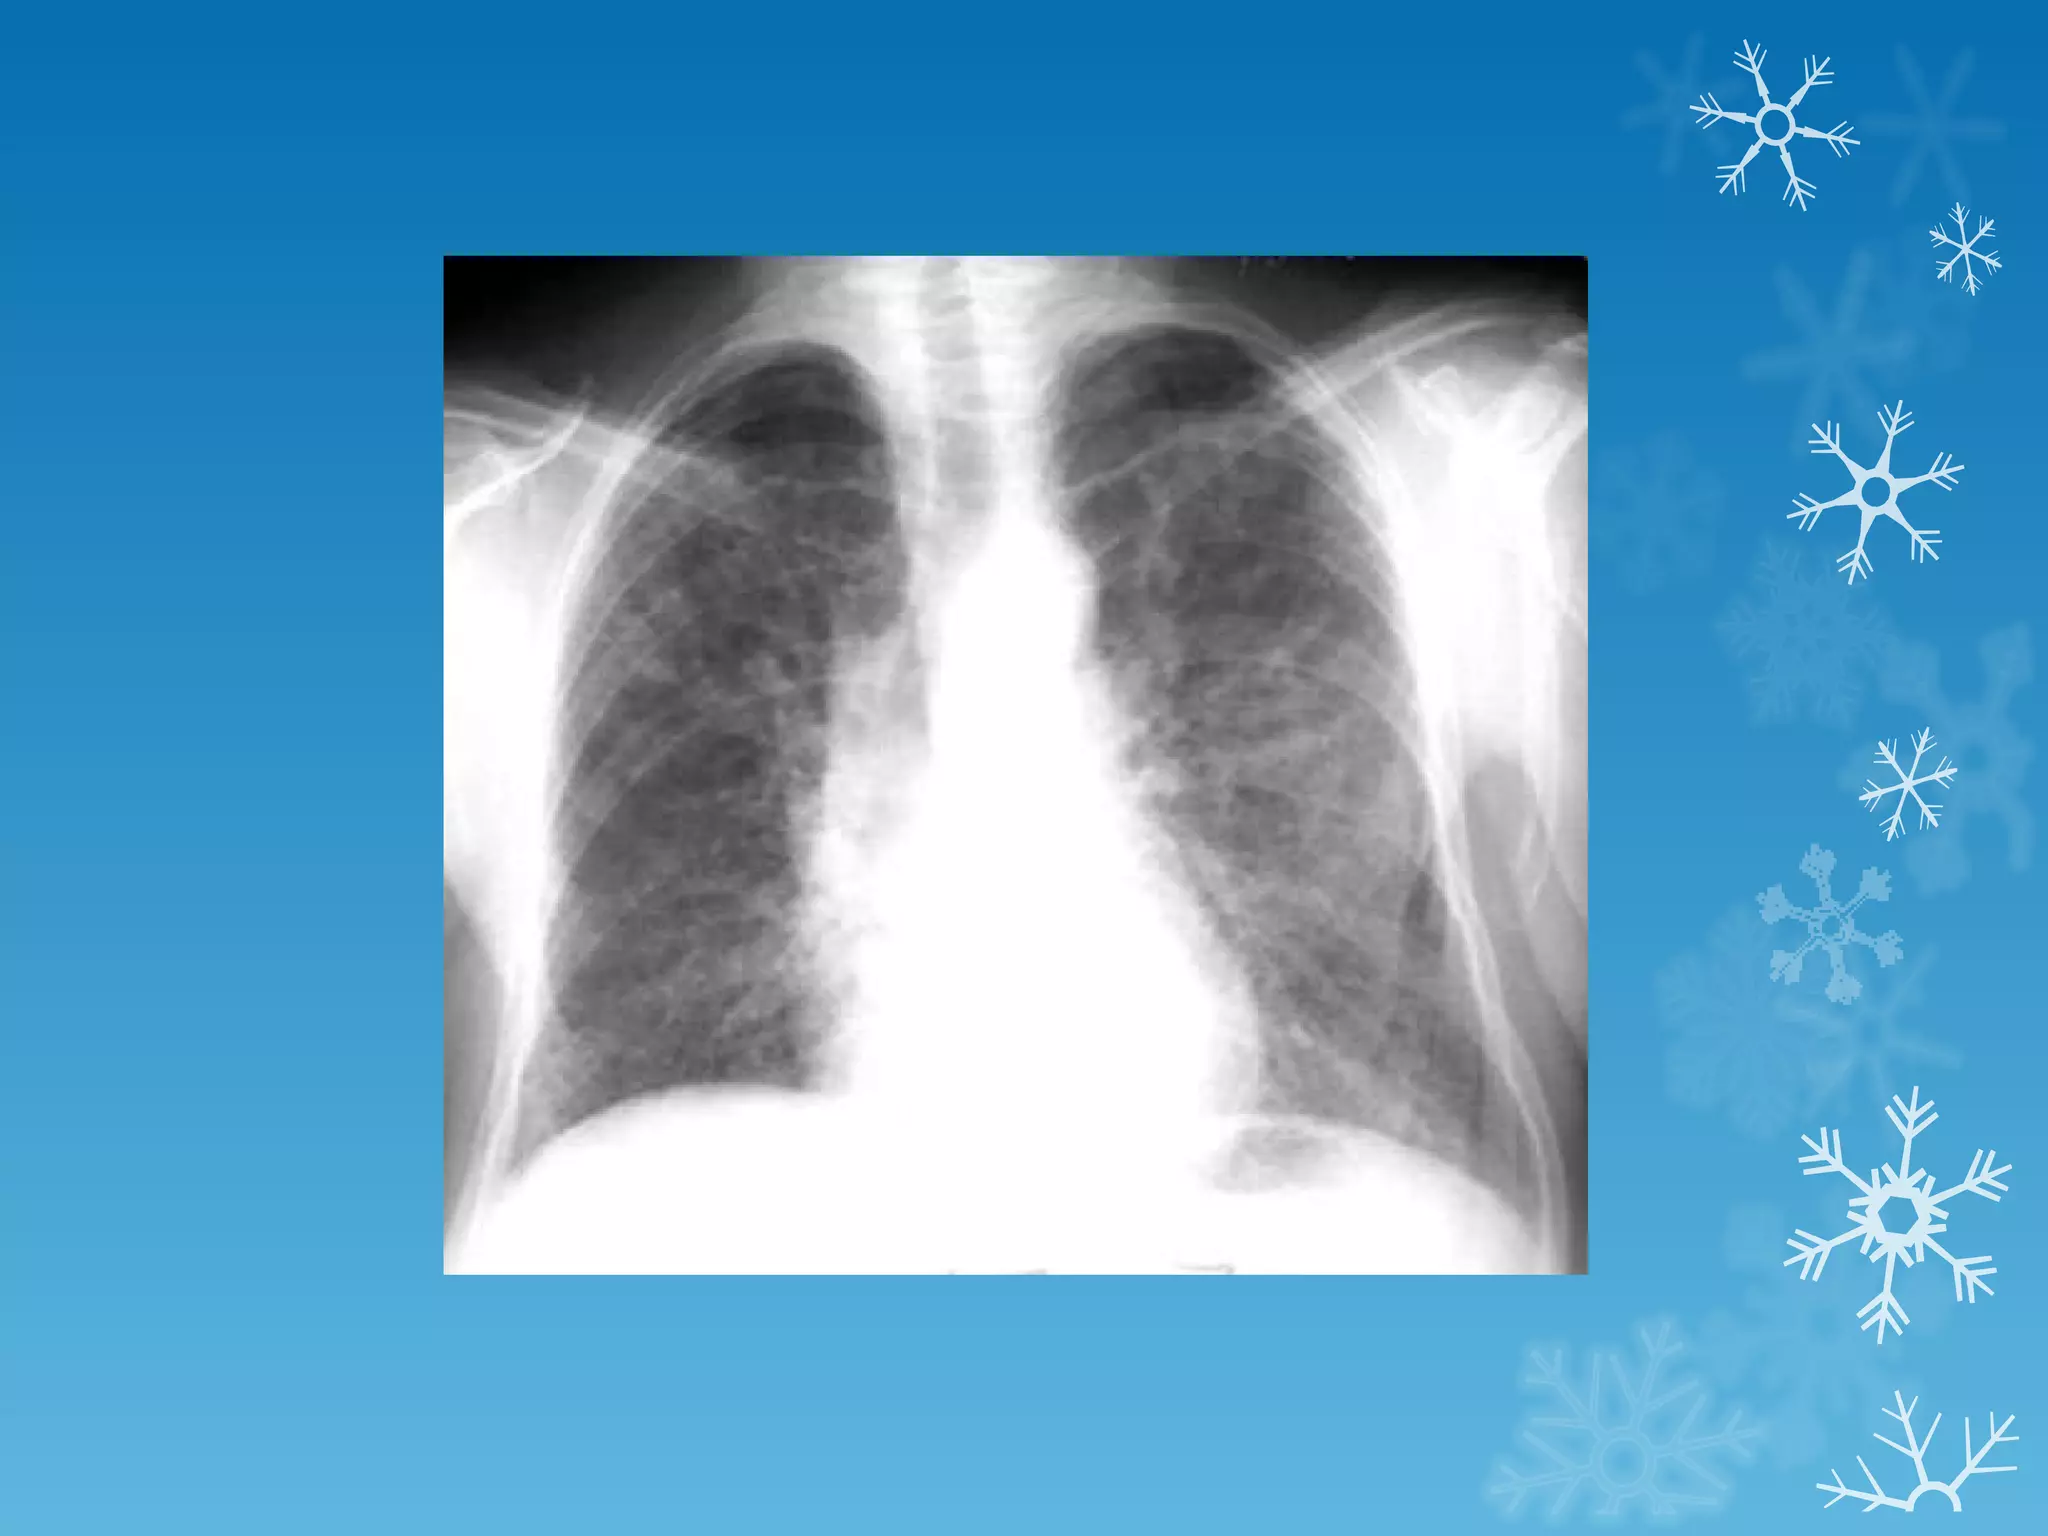

This document discusses chest x-ray interpretation and provides guidance on evaluating x-rays. It explains that tissue density determines how an x-ray beam penetrates, with denser tissues appearing whiter and less dense tissues appearing blacker. It also outlines different chest x-ray views and factors to consider like patient orientation, age, gender, and rotation. Abnormalities are described as appearing too white, too black, too large, or in the wrong place. The document stresses a systematic approach of identifying, localizing, describing lesions, and providing differential diagnoses.